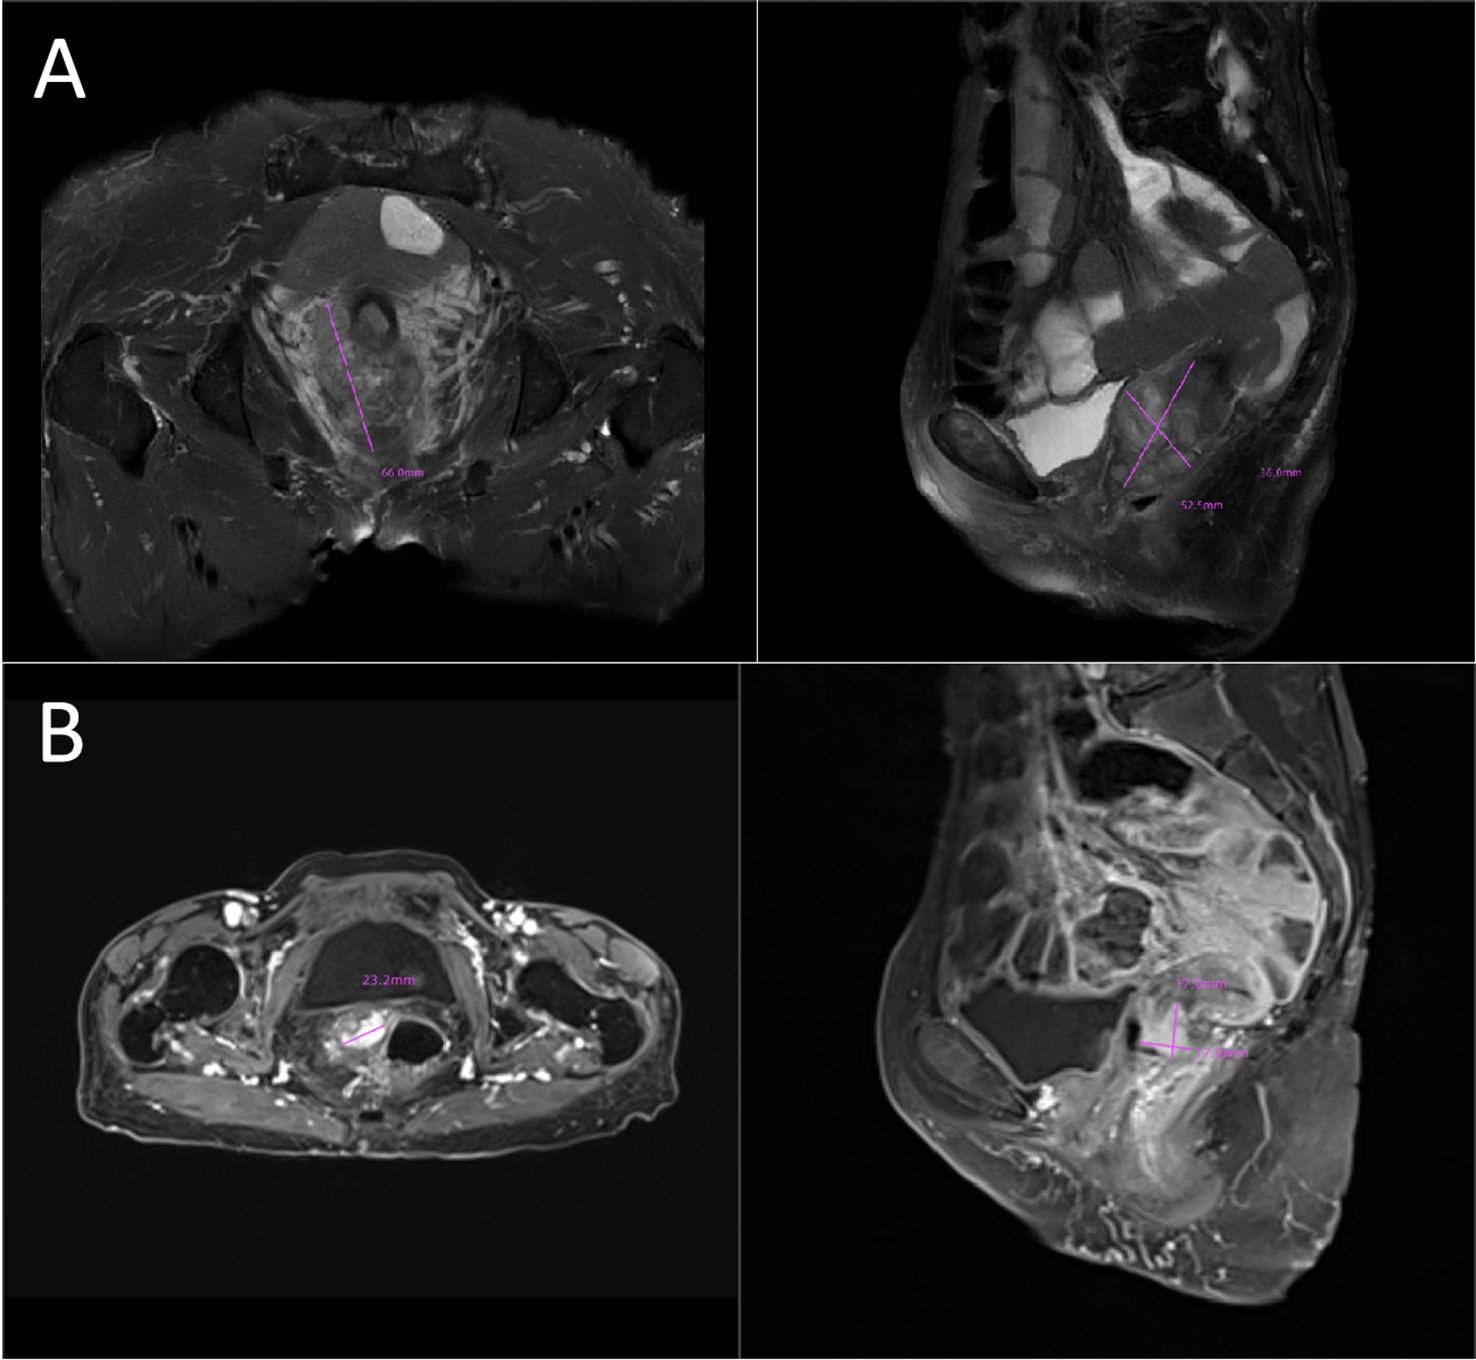

In 2023, a 73-year-old Chinese woman with a prior HPV-DNA test result positive for low-risk HPV type 70 presented to the Department of Internal Medicine of Oncology and Hematology at our hospital. She had been diagnosed with SCC at a local hospital approximately two weeks prior. The patient was in search of alternative treatment options, as she had declined the conventional approaches of radiotherapy and chemotherapy. The patient was admitted to a local hospital due to over 10 days of irregular vaginal bleeding without an immediately identifiable cause. Then, the patient underwent a pelvic magnetic resonance imaging (MRI) scan, which revealed an occupying mass in the anterior lip of the cervix, suggestive of cervical cancer, measuring 66 mm x 52.5 mm x 36 mm. The boundary with the anterior wall of the rectum and the posterior wall of the bladder is unclear (International Federation of Gynecology and Obstetrics (FIGO) stage IV4A) (Figure 1A). The patient subsequently underwent a colposcopic biopsy with hematoxylin and eosin (HE) staining and immunohistochemistry (IHC). The results of these tests were indicative of a predisposition to sarcomatoid carcinoma, leading to the diagnosis of SCC. The sarcomatoid component, as determined by comprehensive histopathological evaluation, accounted for 70% of the total tumor volume in this case (Figures 2, 3). The patient, who was not in favor of undergoing chemotherapy and radiotherapy, decided to seek alternative options and turned to our hospital for further assistance and potential treatment avenues.

Figure 1. (A) Initial tumor mass:MRI image showing an occupying lesion in the anterior lip of the cervix, which is considered to be sarcomatoid carcinoma of the cervix (66mmx52.5mmx36mm). The boundary with the anterior wall of the rectum and the posterior wall of the bladder is unclear (FIGO stage IVA). (B) Post-treatment shrinkage:The pelvic MRI results showed a significant reduction in the size of the patient’s tumor (23.2mmx17.8mmx17.0mm). MRI, magnetic resonance imaging.

SCC is extremely rare and has a poor prognosis in advanced stage patients, with no evidence of survival benefit from radiotherapy and chemotherapy. We advised the patient to undergo genetic testing to identify potential therapeutic targets that could inform a more personalized treatment approach. The genetic testing of the patient’s tumor tissue revealed the following mutations and characteristics (1): Somatic tumor mutations:An NRAS Q61K mutation was detected at a frequency of 6%;A BRAF G464E mutation was identified at a frequency of 6.9%;An ABL1 K609del mutation was identified at a frequency of 6.0%; A DNMT3A S129G mutation was identified at a frequency of 48.2%; An EPCAM A82G mutation was identified at a frequency of 48.8%; A PALB2 A38G mutation was identified at a frequency of 42.5% (2). The tumor’s Combined Positive Score (CPS) for PD-L1 expression was 45, indicating positive programmed death-ligand 1 (PD-L1) expression (Figure 4) (3). No genes associated with hyperprogressive disease (HPD) were found (4). No mutations were detected in either immunotherapy-positive associated genes (MMR-related genes, POLE, POLD1, DDR genes, KRAS, TP53) or immunotherapy-negative associated genes (B2M, DNMT3A, JAK1/2, ALK, ROS1, MET, VEGFA, PTEN, STK11) (5). The microsatellite instability (MSI) testing results indicate a microsatellite stable (MSS) status, with an MSI score of 0.0235 (values ≥0.4 classified as MSI-H, <0.4 as MSS). The CPS for PD-L1 expression indicates that the tumor is highly likely to be sensitive to ICIs, which could make immunotherapy a viable treatment option. Prior to initiating formal antitumor therapy, the patient underwent comprehensive biochemical testing. The baseline characteristics upon hospital admission are detailed in Table 1. As a result, the patient was administered a combination therapy consisting of bevacizumab (300 mg) plus pembrolizumab (200 mg) Q3W. After 2 cycles of the therapeutic regimen, the tumor shrank significantly, and the patient did not experience any side effects(Figure 1B). Since then, the patient has continued to receive the regimen and the tumor has continued to shrink. Ultimately, after completing 10 cycles of treatment with ICIs and anti-angiogenic drugs, the positron emission tomography/computed tomography (PET-CT) scan showed complete disappearance of the tumor, with no evidence of residual cancer in the body(Figure 5). Considering the patient’s advanced stage and the high malignancy of cervical sarcomatoid carcinoma, which is highly prone to recurrence, we continued with the original treatment plan for maintenance therapy. During the maintenance therapy period, the patient underwent regular follow-up evaluations without evidence of recurrence. Treatment was maintained for 13 months until MRI demonstrated recurrence (Figure 6). Subsequently, the patient was transferred to the Department of Radiotherapy in our hospital and began radiotherapy. We still conducted regular follow-ups for the patient. Given the extremely high malignancy of this rare tumor, although the tumor eventually recurred unfortunately, the combination therapy initially achieved a transient recurrence-free survival period. Moreover, no significant adverse reactions were observed during the drug treatment. Radiotherapy was discontinued after 3 months due to concurrent tumor progression observed during treatment. The patient is currently receiving palliative care only. Our data demonstrate a progression-free survival (PFS) exceeding 13 months and overall survival (OS) surpassing 22 months.